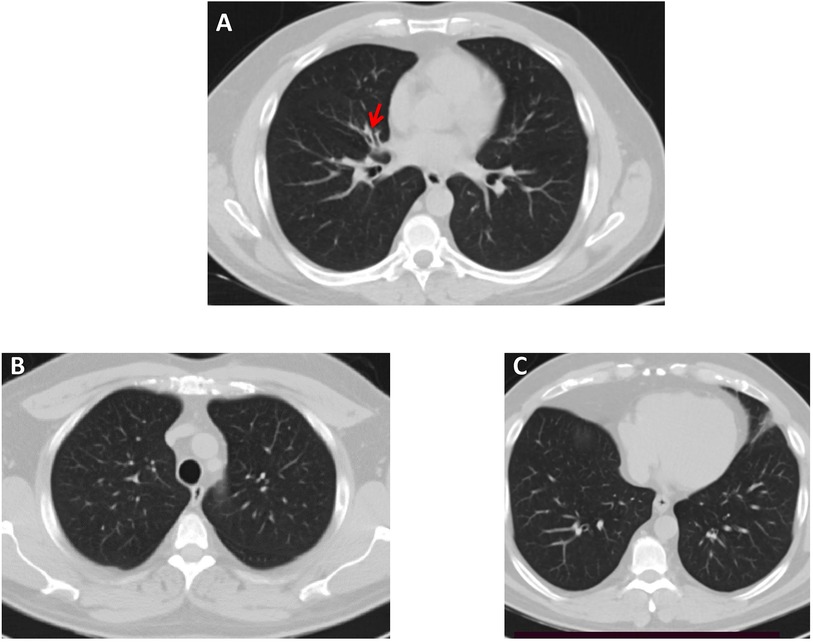

Importantly, both patients reported that they also suffer from respiratory symptoms characterized by chronic sinusitis and chronic wet cough since infancy (Table 1) and therefore, they were referred to a pulmonology clinic for further evaluation and follow-up. As shown in Figure 2, a chest computerised tomography (CT) scan of patient 2 revealed a localized area of bronchiectasis in the medial segment of the right middle lobe of the lung. Moreover, cystic bronchiectasis accompanied by mucus plugging was also observed, particularly in the lower lobes. There were no signs of laterality defects in the CT scan, which was expected based on the patient's medical history. Patient 1 refused to be evaluated for the respiratory symptoms.

CT scans of the chest are shown in three panels labeled A, B, and C. Panel A highlights a small nodule in the right lung with a red arrow. Both panels B and C show a normal chest anatomy with clear lung fields.

Figure 2. High-resolution chest CT scan—lung window, of Patient 2. (A) A small area of bronchiectasis in the medial segment of the right middle lobe, indicated by a red arrow. (B,C) Both lung fields in the upper and lower lobes appear normal.

While CFAP43 protein is implicated in both ciliary and flagellar structure and function, reported cases with CFAP43 genetic variations have not typically exhibited clinical manifestations of ciliary dysfunction in the airways. In our study, both patients exhibited symptoms consistent with respiratory ciliary dysfunction, including chronic sinusitis and chronic wet cough since early infancy. Additionally, chest CT scan revealed bronchiectasis, providing further evidence of ciliary impairment. Notably, previous reports have documented a similar clinical presentation, wherein variations in genes initially associated with MMAF, such as SPEF2 and CFAP47, were identified as the underlying cause for both ciliary and flagellar phenotypes (11, 12). These reports indicate that defects in some MMAF genes may cause a phenotypic spectrum ranging from MMAF without respiratory manifestations to infertile patients with PCD-like symptoms.